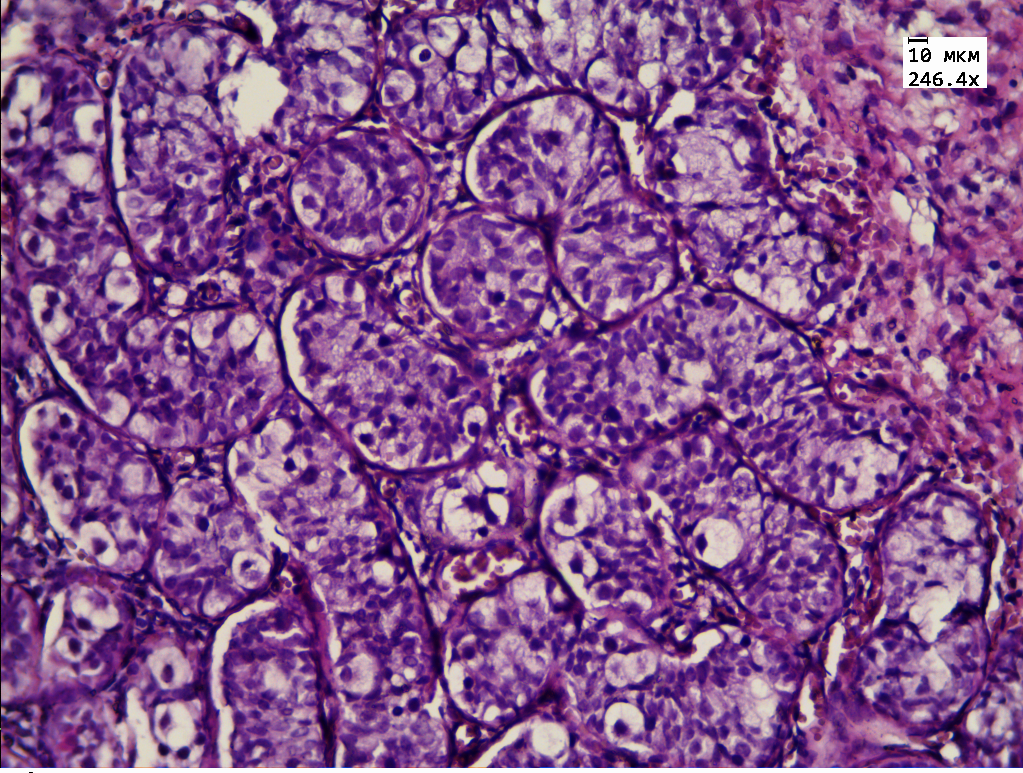

Гистологическое исследование интраоперационного материала гонад показало наличие ткани яичка и яичника, разделенных фиброзной прослойкой. Ткань яичника фиброзирована, деление на корковый и мозговой слой нечеткое. В корковом слое определяются примордиальные фолликулы с выраженными дистрофическими изменениями (рис. 1, на цв. вклейке). Ткань яичка разбита на дольки фиброзными прослойками, единичные микрокальцинаты. В эпителии канальцев резко выраженные дистрофические и пролиферативные изменения: увеличение размеров клеток, ядер, гиперхромия ядер. Клетки сперматогенного эпителия располагаются хаотично и находятся в разной степени зрелости. Обращают на себя внимание крупные клетки с четко определяемым ядром и наличием в нем ядрышек — половые клетки (рис. 2, на цв. вклейке). Такое строение сперматогенного эпителия соответствует организации, характерной для антенатального периода [4].

Рис. 1. Микроскопическая картина ткани яичника: диф- ференцировка на корковый и мозговой слой, в корковом слое примордиальные фолликулы с дистрофическими изменениями. Окраска гематоксилином и эозином, ув. 250.

Результаты гистологического исследования гонад нашего пациента показали наличие незрелой тестикулярной ткани с выраженными пролиферативными изменениями, микрокальцинатами. В ткани яичника отсутствовало четкое деление на корковое и мозговое вещество. Примордиальные фолликулы, определяемые в овариальной части гонады, имели выраженные дистрофические изменения. На основании этих данных было принято решение о проведении гонадэктомии.